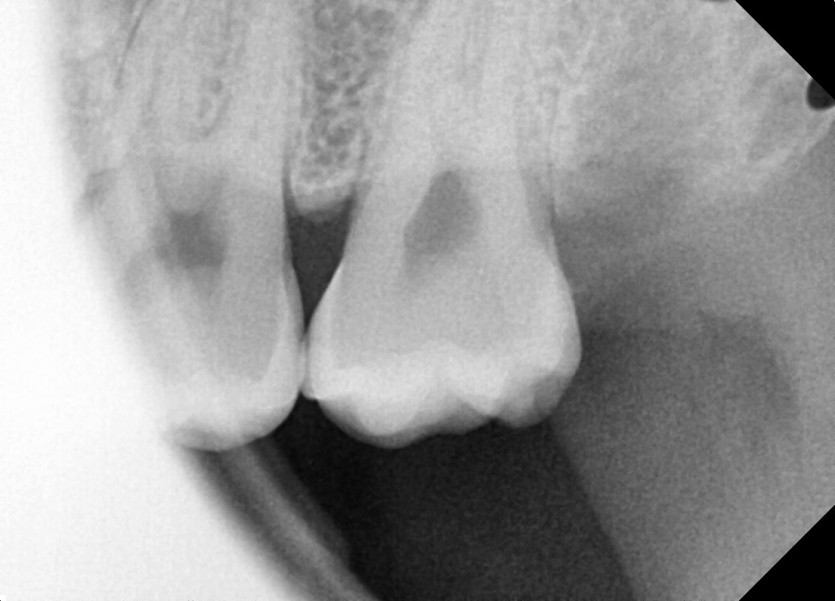

#28,38 사랑니 발치

구강 외과 전문의가 당일 발치했습니다.